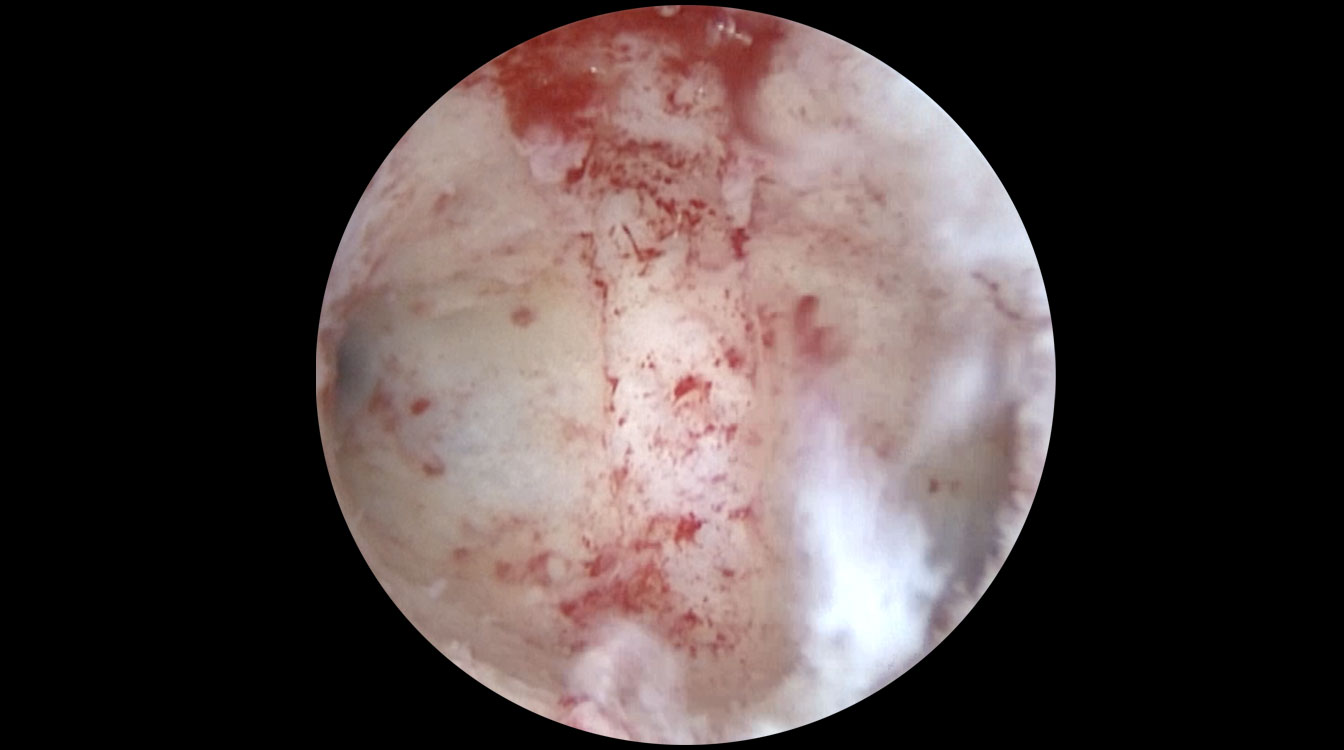

Histeroscopia reprezintă o etapă importantă în cadrul investigațiilor efectuate pacientelor ce prezintă diagnosticul de infertilitate. Histeroscopia poate identifica modificări subtile ale cavității uterine, ce nu pot fi diagnosticate prin ecografie, ceea ce face ca această inervenție să devină extrem de utilă la pacientele cu infertilitate. Un exemplu poate fi reprezentat de inflamația cronică a endometrului, situație numită endometrită (Fig. 9, 10).